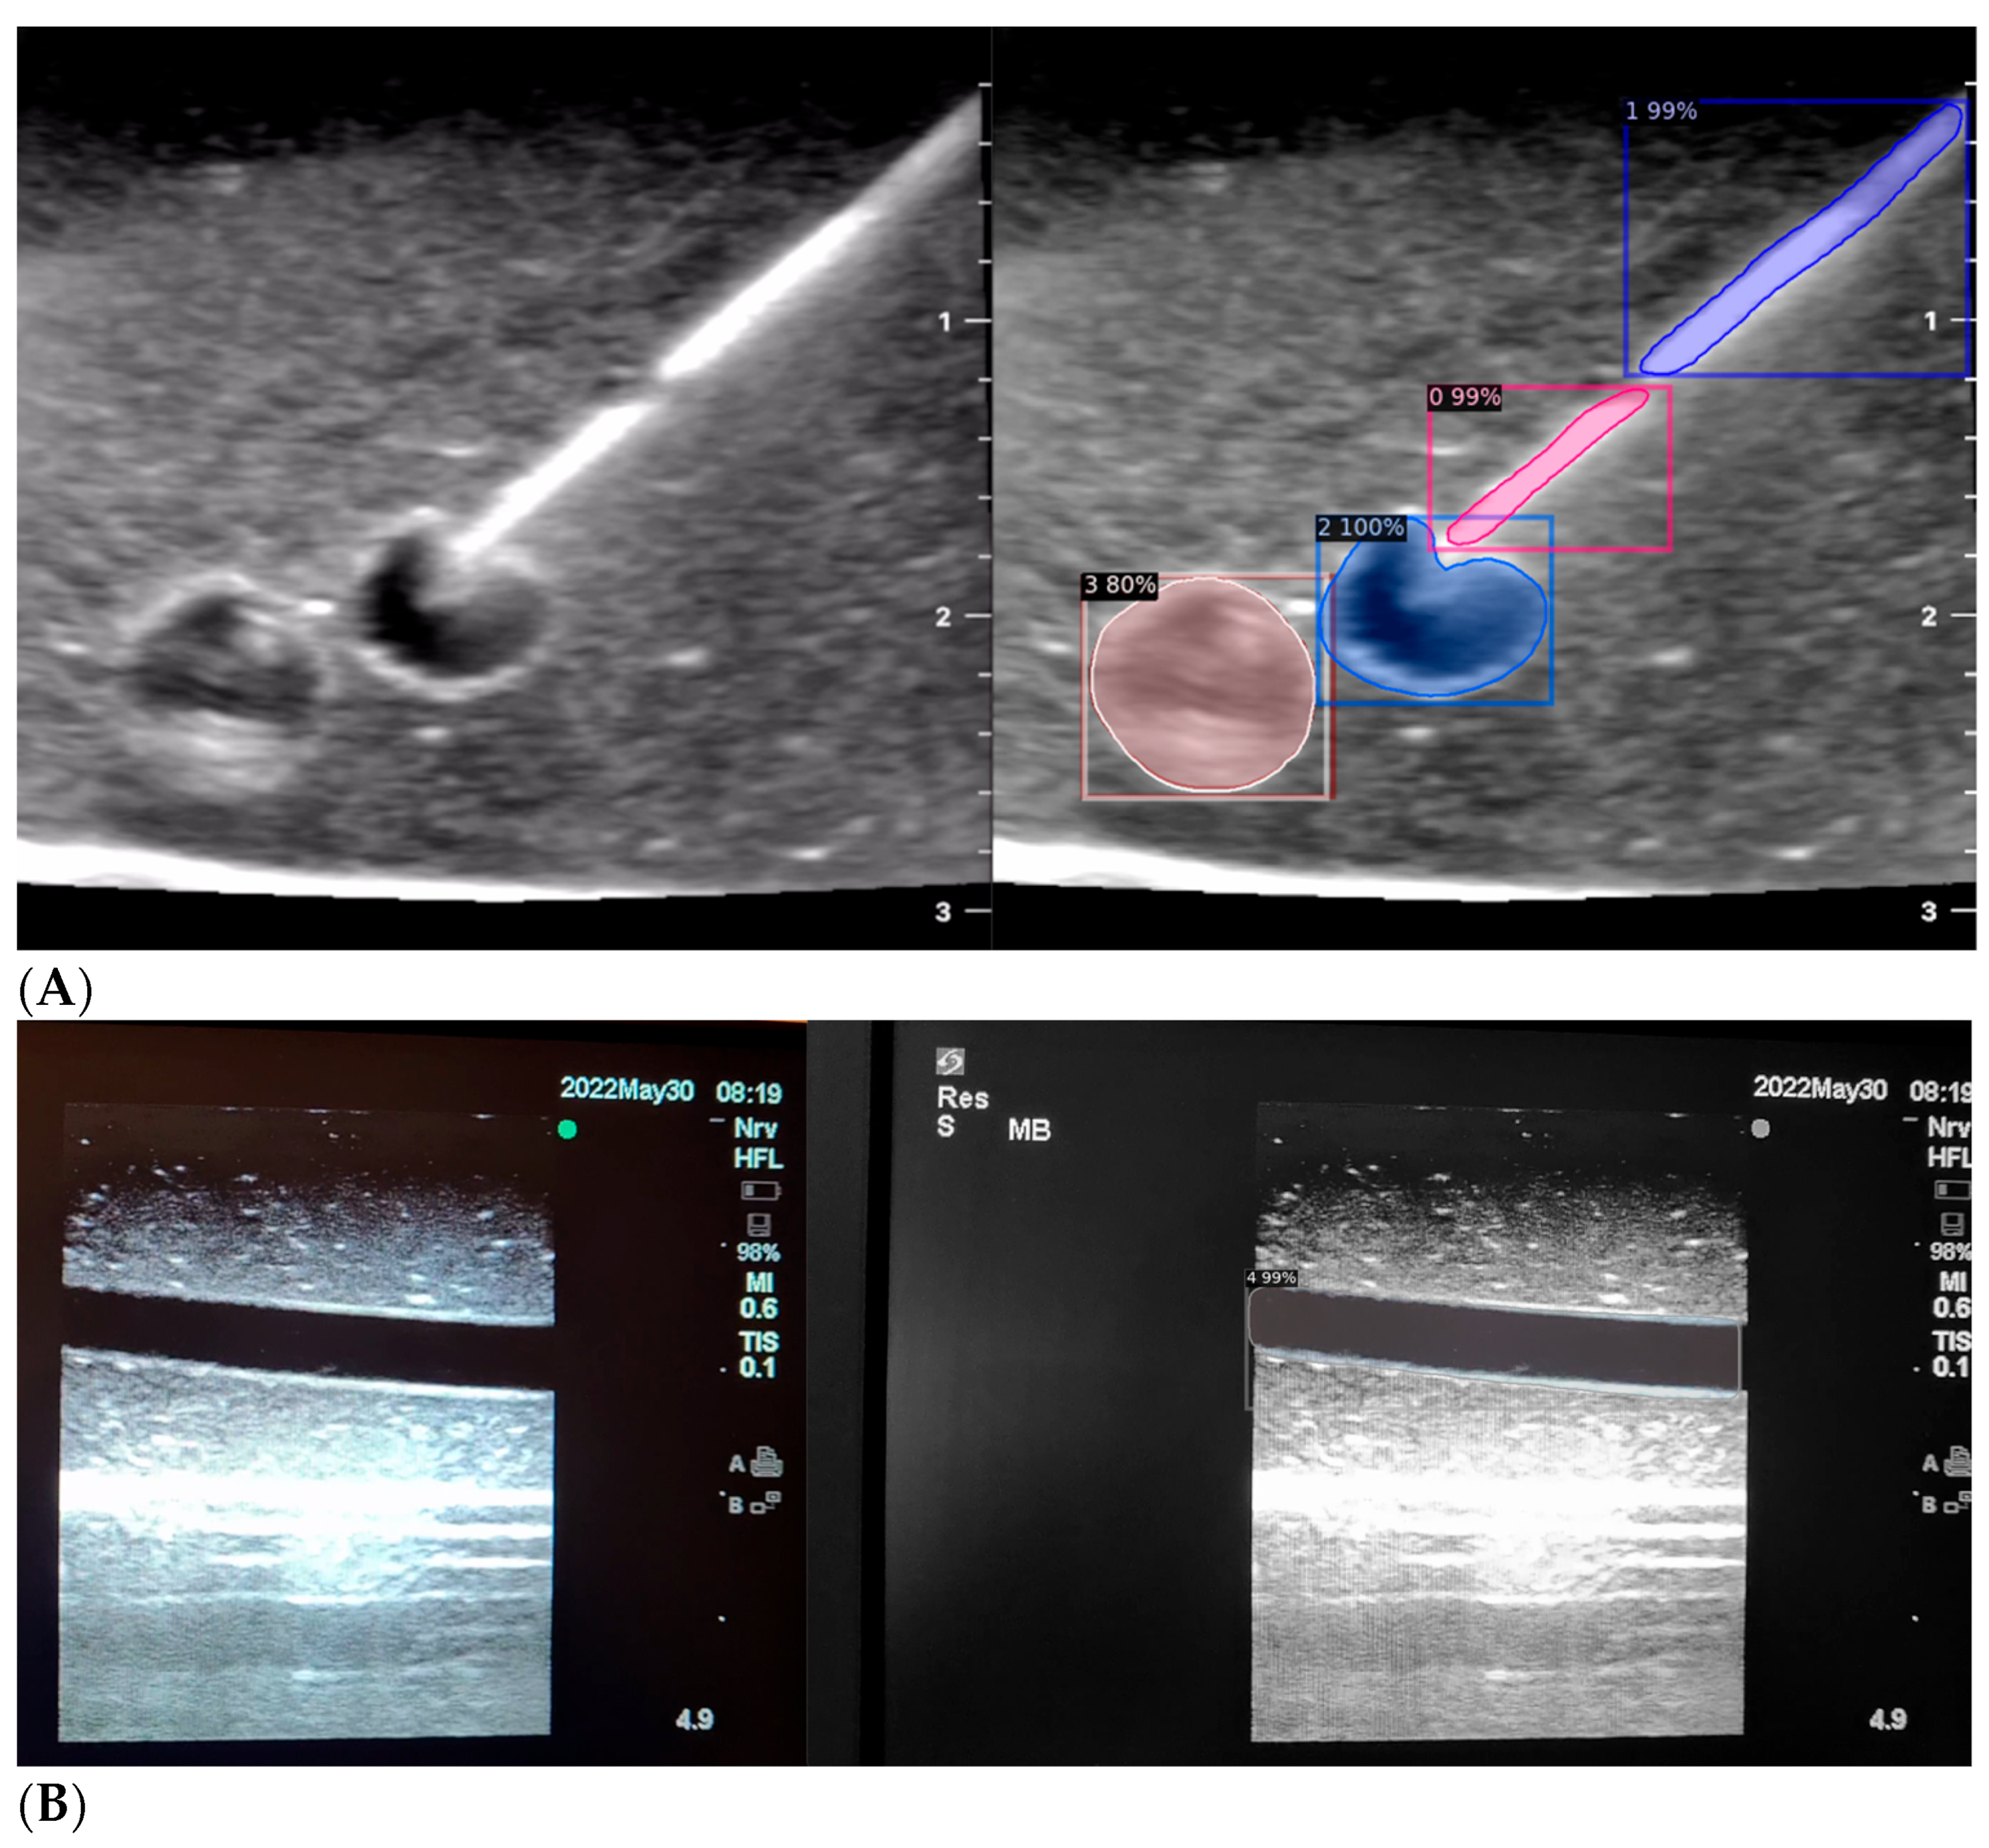

When the model is applied, the original ultrasound image is overlaid with a new layer that presents the detection results, offering insights into predicted target areas (Figure 4 and Figure 5).

The segmentation area represents the region identified by the model as each object class (needle tip, needle body, blood vessel, or nerve bundle). This area is visually highlighted, allowing for a clear understanding of what structure is of interest. To provide additional context, a bounding box in the shape of a square is placed around the segmentation area, enclosing the detected object and providing a concise representation of its location. These are illustrated in Figure 4, Figure 5 and Figure 6, with original images on the left and overlayed images on the right for our three different phantom models.

To facilitate easy differentiation between different objects, Detectron2 generates a detection name based on the metadata of the COCO file. This name provides information about the specific object type, enabling the effective categorisation and analysis of different structures.

In order to assess the confidence level of the model’s predictions, a confidence percentage is assigned for each object class labelled (Figure 4, Figure 5 and Figure 6). This percentage represents the probability of a true positive detection by the model. It quantifies the model’s level of certainty regarding the accuracy of its prediction for each detected defect.

Figure 5. Model inference in Phantom B (Agar 2.5% with septanol).